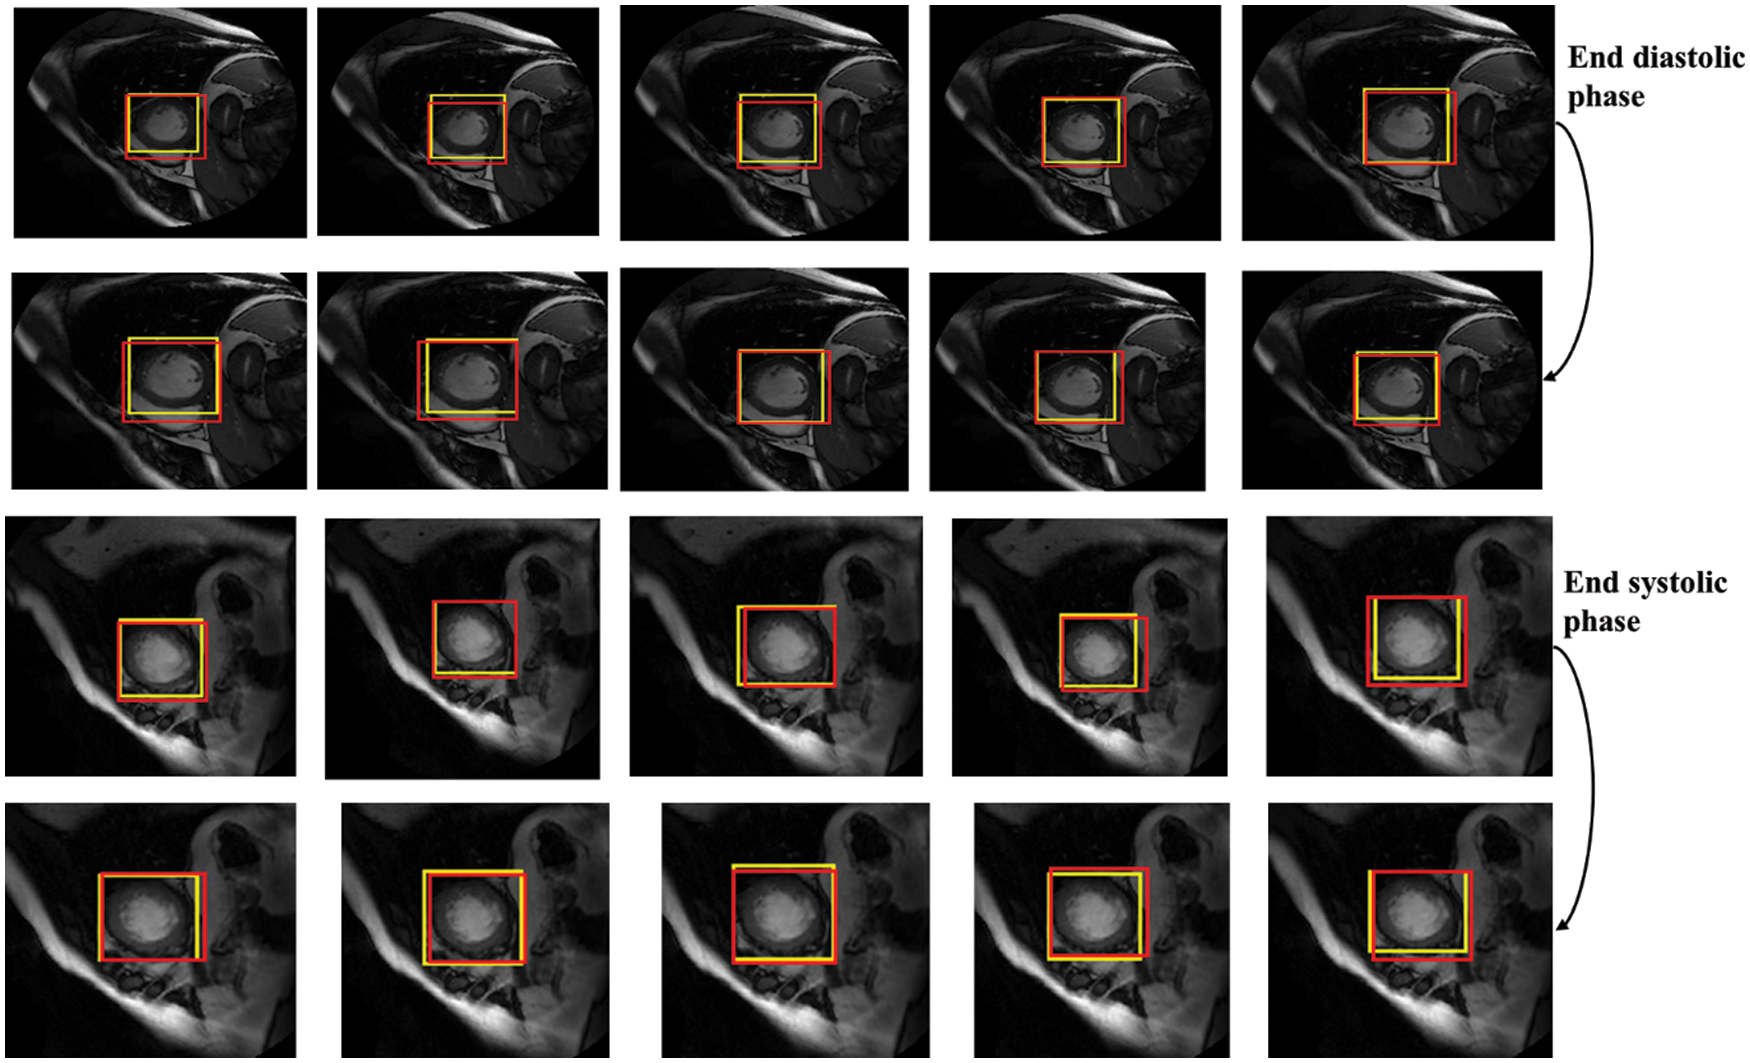

In terms of LV detection, the proposed network outperforms the R-CNN network. Tab. 3 shows the performance evaluation for the proposed model utilizing a cardiac cycle of 20 slices at end-diastolic and end-end systolic phases. Fig. 8 depicts the proposed network’s visual detection results, with yellow rectangles representing ground truth (labels) and red rectangles representing outcomes of the proposed detection model. The greater the overlapping, the better the network performs. The results reveal that the suggested technique can recognize the LV area and myocardium with high accuracy thanks to the Faster R-CNN that combines candidate region proposals, classification, and regression algorithms.

Figure 8: Detection results of the proposed network in different slices, the yellow rectangles represent ground truth (labels) and red ones represent results of the proposed detection model

The results of the proposed network achieved efficient LV detection with accurate detection at various shapes and sizes of the LV during end-diastolic and end-systolic phases. The detection method has an adaptability to different individuals. Hence, it can achieve a more efficient performance utilizing RPN than R-CNN. Based on the detection of LV using the proposed network, the LV region can be cropped for segmentation and classification with less computational cost and time.